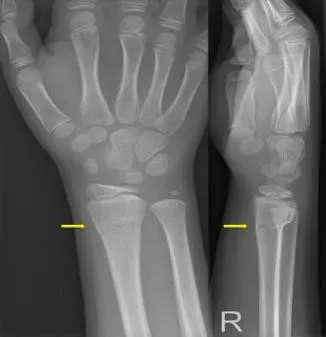

- Röntgenfoto: dit is het belangrijkste onderzoek. Op de foto is doorgaans duidelijk te zien of er een breuk is en wat voor type. Bij kinderbreuken kijkt men goed naar afwijkingen in de contour van het bot: een buiging of kleine breuklijn kan al duiden op een greenstick of torusfractuur. Ook wordt gelet op de groeischijven om te zien of die vrij zijn van letsel.

- Greenstick-fractuur (groenhoutbreuk): het bot is aan één zijde gebroken en aan de andere zijde alleen gebogen, net als een jong groen takje van een boom dat je breekt. Het bot blijft gedeeltelijk intact.

- Torusfractuur (twijgbreuk): hierbij is het bot niet echt gebroken, maar ingedeukt of geplooid, alsof het bot een deukje heeft opgelopen. Dit komt vaak voor aan het uiteinde van de onderarmbeentjes bij een val.